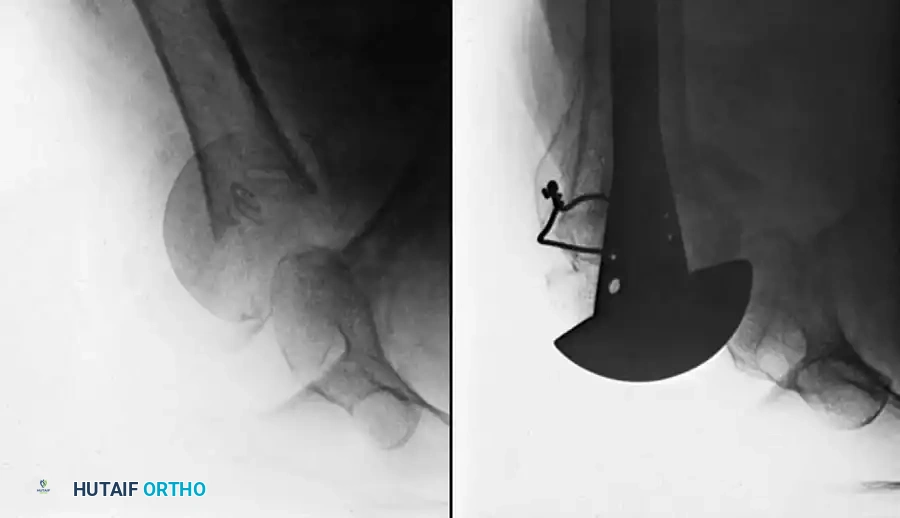

Technique 56-8: Bone Graft of Tibial Nonunion (Banks Technique)

- Exposure: Expose the nonunion through a medial longitudinal incision 10 cm long.

- Preparation: Freshen the fracture surfaces by removing sclerotic bone to create a wedge-shaped defect with its apex directed toward the articular surface of the ankle. Ensure damage to the articular cartilage is minimal.

- Reduction and Fixation: Restore the fragments to their normal anatomic position. Hold them gently with a large pointed reduction forceps (towel clip) and fix them with a 4.5 mm cortical or 4.0 mm cancellous lag screw.

- Window Creation: Make a cortical window in the tibial metaphysis at the proximal end of the surgical wound by removing a square piece of bone with its edges undercut.

- Grafting: Harvest cancellous bone through this window using a curette. Pack this autologous cancellous bone tightly into the wedge-shaped defect at the nonunion site.

- Closure: Replace the square piece of cortex over the metaphyseal window and close the wound in layers.

Fig. 56-19 Technique for grafting nonunion of medial malleolus (Banks).

Postoperative Protocol: The aftertreatment is identical to that of the sliding graft technique.